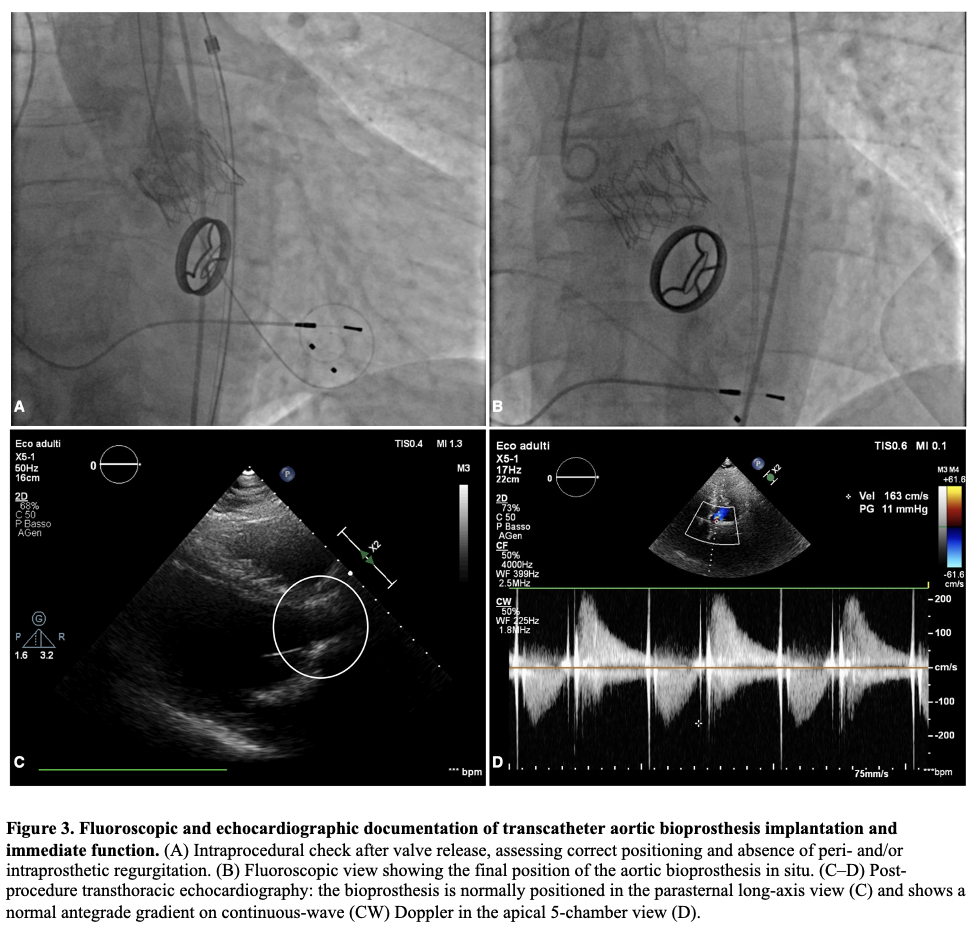

BACKGROUND: Thrombocytopenia is common after transcatheter aortic valve implantation (TAVI) and is often a self-limited procedural phenomenon. In patients requiring peri-procedural heparin bridging, the early platelet drop may raise concern for heparin-induced thrombocytopenia (HIT) and prompt potentially hazardous changes in anticoagulation. CASE PRESENTATION: A 73-year-old man with permanent atrial fibrillation and a mechanical mitral valve on vitamin K antagonist (VKA) underwent transfemoral TAVI for symptomatic severe paradoxical low-flow/low-gradient aortic stenosis. Unfractionated heparin (UFH) bridging was started 4 days before TAVI. The procedure was uncomplicated. Platelets declined from 177×10^3/µL (pre-TAVI) to 113×10^3/µL on day 0, 106×10^3/µL on day +1, with a nadir of 75×10^3/µL on day +3 (−58%), then recovered to 114×10^3/µL by day +7. Haemoglobin decreased from 12.0 to 9.5 g/dL without overt bleeding; vascular access ultrasound excluded haematoma, pseudoaneurysm and arteriovenous fistula. Fibrinogen remained within the normal range (about 230–400 mg/dL). Clinical probability for immune HIT was low (4Ts ≤3) and an anti-PF4/polyanion immunoassay was negative. Given the very high thrombotic risk, UFH was continued as bridging while VKA was restarted, then UFH was stopped after reaching the therapeutic INR. Post-procedural echocardiography confirmed a normally functioning transcatheter valve without significant leak. CONCLUSIONS: An early, marked platelet fall after TAVI—especially with day 0–3 nadir and rapid recovery—may represent a procedural “pseudo-HIT” pattern rather than immune HIT. Integrating timing, pre-test probability and anti-PF4 testing can avoid unnecessary heparin discontinuation or unsafe anticoagulation interruptions in patients with mechanical valves.